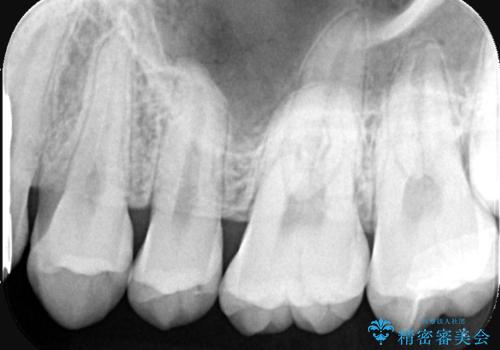

上顎左側第二大臼歯頬側面から遠心面、咬合面にもう蝕が波及していたためアンレー形態となりました。

セラミックアンレーセット時、ラバーダム防湿を行っています。